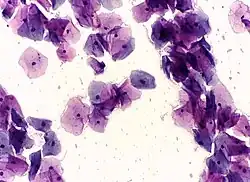

Normal squamous epithelial cells in premenopausal women -

Atrophic squamous cells in postmenopausal women